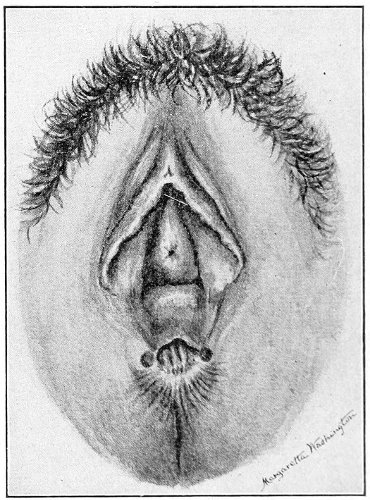

Fig. 16.—Appearance of the external genitals in a woman with gonorrhea: G. m., gonorrheal macula situated at the base of a vaginal caruncle.

Suppuration of the duct may be demonstrated by pressing over the course of the duct, when a drop of pus will escape from the opening. In such cases the orifice of the duct is usually surrounded by a red areola, resembling a flea-bite, which has been called the gonorrheal macula (Fig. 16). This macula persists long after all other traces of inflammation about the vulva and vagina have disappeared, and after all frank suppuration in the duct has subsided. Its presence indicates at least the probability of previous gonorrheal infection.